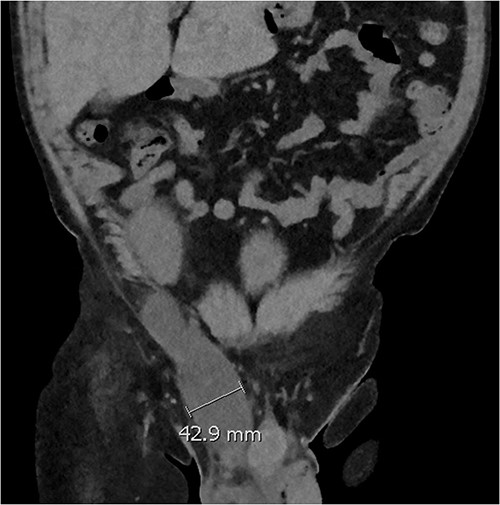

Coronal CT scan showing lobulated low-density fluid collection adjacent to the lower pole of the transplant kidney in the right iliac fossa and extending into the superficial inguinal canal tracking along the inguinal and scrotal hernia with a maximal width of 43 mm in transverse diameter.

Five days later, the patient had another ultrasound and an ensuing CT KUB given recurrence of a painful groin swelling overnight. It showed a reaccumulation of the pelvic fluid collection, which extended into the groin toward the scrotum with two pockets of fluid collection measuring 4.6 × 6.5 × 2.7 cm (42 ml) and 7.7 × 3.5 × 4.6 cm (66 ml) (Figs 2 and 3). We temporized the situation by aspirating 35 ml of fluid by the bedside under ultrasound guidance for symptom relief and booked him for an elective operation given the complex anatomy of the collection.